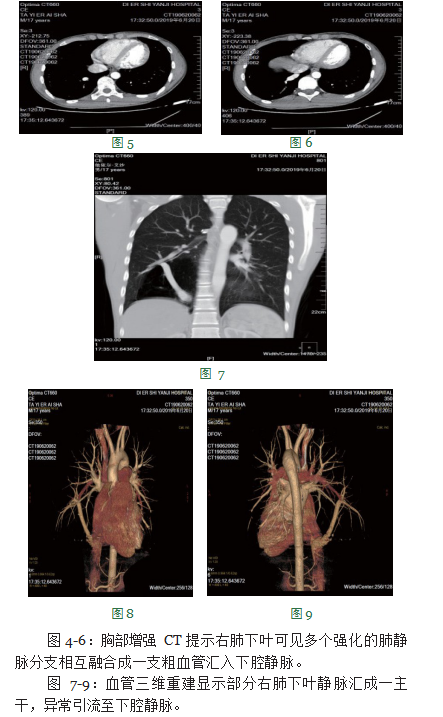

患者男,17岁,维吾尔族。患者缘于2018年6月因左耳血管瘤在焉耆县医院行手术治疗,术前行胸部CT检查提示右肺下叶局限性肺气肿,建议1年后复查,当时无发热、咳嗽、咳痰、咯血、活动后气短等伴随症状,出院后亦无任何不适症状。患者于今年6月就诊于新疆医科大学第一附属医院,行胸部CT检查提示:右肺下叶局限性肺气肿、右肺中叶散在小结节,考虑炎性肉芽肿性病变,建议短期抗感染治疗后复查,患者遂来我院门诊,要求输液治疗。我院门诊医生仔细阅片后,发现其右肺下叶疑似存在动静脉畸形,建议行胸部增强CT检查,经与患者家属协商后,于次日在我院做胸部增强CT,结果显示右肺下叶可见一粗大血管自上而下引流进入下腔静脉,周围肺组织透光明显增强,诊断为右下肺静脉发育异常(弯刀综合征)并右肺下叶发育不良(肺气肿)。